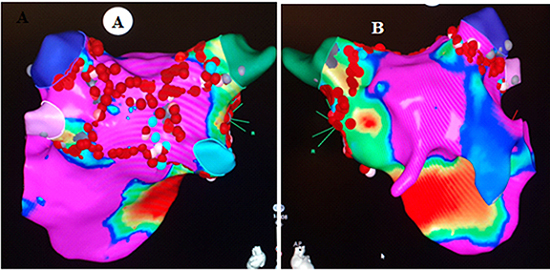

Positioning the Vizigo Sheath right at the septum proved to be successful, following which a bidirectional ablation catheter was used to create a map (with Carto mapping system) of the LA. Following movement of the ablation catheter, patient developed AF, which appeared typical with proximal to distal activation. Patient was cardioverted to maintain stability during mapping. Superior and inferior pulmonary veins and the LA appendage were identified. Once the activated coagulation time was noted to be therapeutic, left superior and inferior pulmonary veins were isolated in pairs followed by the right superior and inferior pulmonary veins. Fractionated electrograms and abnormal voltages were noted on the posterior wall during LA mapping; hence a posterior box isolation was done as well. Since the Vizigo sheath was right at the septum a circular catheter could not be advanced to confirm exit block. Pacing around every ablation lesion to ensure loss of capture was done followed by Adenosine testing.

Figure 4(A+B). Electroanatomical mapping (Carto ® system) A. postero-anterior view showing PVI lines and the posterior box B. antero-posterior view